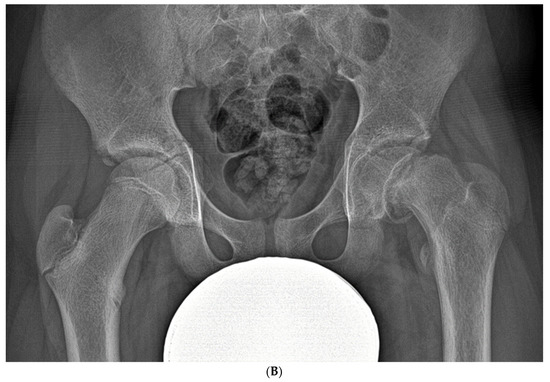

Basic Differences and Most Common Findings in Ultrasound Examinations of Musculoskeletal System in Children: A Narrative Literature Review

by Tomasz Poboży, Wojciech Konarski, Karolina Piotrowska-Lis, Julia Domańska, Kamil Poboży and Maciej Kielar

Healthcare 2022, 10(10), 2010; https://doi.org/10.3390/healthcare10102010 - 12 Oct 2022

We present basic differences in the musculoskeletal ultrasound examinations between adults and children. Examiners who deal with adults on a daily basis have shared concerns about examining children. Such concerns may arise from the different approach to child ultrasounds, but they also come [...] Read more.

We present basic differences in the musculoskeletal ultrasound examinations between adults and children. Examiners who deal with adults on a daily basis have shared concerns about examining children. Such concerns may arise from the different approach to child ultrasounds, but they also come from differences in anatomical characteristics according to developmental age. We discuss the presence of growth plates, as well as non-mineralized parts of the bones. We also refer to the pathologies most often found in ultrasounds in early developmental stages. In the PubMed database, the set of keywords: “msk ultrasound in children”, “pediatric msk sonoanatomy”, “coxitis fugax”, “pediatric Baker’s cyst”, “Baker’s cyst ultrasonography”, “bone septic necrosis in ultrasonography”, “ultrasonography in juvenile idiopathic arthritis”, and “ultrasonography in juvenile spondyloarthropathies”, was used to identify a total of 1657 results, from which 54 was selected to be included in the article. We discuss the problem of osteochondritis dissecans, Osgood-Schlatter disease, examples of ligament injuries (especially in relation to the knee and ankle joints), exfoliation of growth cartilages, osteochondroma, exudates and inflammations affecting joints, and Baker’s cysts. In this way, we have collected useful information about the most common diseases of the musculoskeletal system in children. Full article

Show Figures

Figure 1